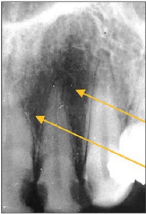

28. What is showing by arrow?

29. What is shown by the arrow?